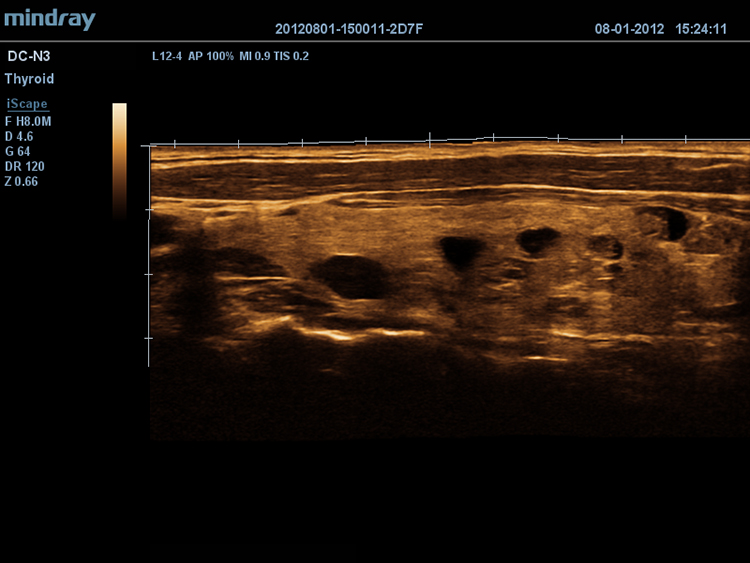

iScapeTM

–î–∞–µ—Ç –ø–æ–ª–Ω—ã–π –∏ —Ä–∞—Å—à–∏—Ä–µ–Ω–Ω—ã–π –æ–±–∑–æ—Ä –∞–Ω–∞—Ç–æ–º–∏—á–µ—Å–∫–∏—Ö —Å—Ç—Ä—É–∫—Ç—É—Ä –ø–æ—Å—Ä–µ–¥—Å—Ç–≤–æ–º –ø–∞–Ω–æ—Ä–∞–º–Ω–æ–π –≤–∏–∑—É–∞–ª–∏–∑–∞—Ü–∏–∏, –≤ —Å–æ—á–µ—Ç–∞–Ω–∏–∏ —Å –∏–Ω–¥–∏–∫–∞—Ç–æ—Ä–æ–º —Å–∫–æ—Ä–æ—Å—Ç–∏ –∏ —Ñ—É–Ω–∫—Ü–∏–µ–π –ø—Ä—è–º–æ–≥–æ / –æ–±—Ä–∞—Ç–Ω–æ–≥–æ —Å–∫–∞–Ω–∏—Ä–æ–≤–∞–Ω–∏—è, –¥–µ–ª–∞—è –ø—Ä–æ—Ü–µ—Å—Å –±–æ–ª–µ–µ –ª–µ–≥–∫–∏–º, –ø–æ—Å–ª–µ–¥–æ–≤–∞—Ç–µ–ª—å–Ω—ã–º –∏ —É–ø—Ä–∞–≤–ª—è–µ–º—ã–º.